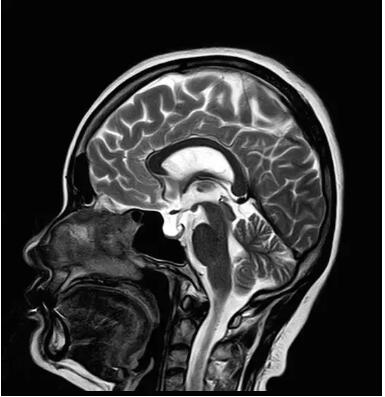

佳能磁共振推出了全新一代Vantage Elan1.5T磁共振,這款日本原裝進口的 1.5T磁共振,集當今磁共振創(chuàng)新科技成果于一身:

高精度鍍膜新磁體——鍍膜貼合技術 獲得最佳磁場均勻度

3DRSCE微雕梯度 ——精準控制頻率和相位輸出理想波形

Pure 射頻影像鏈——圖像信噪比提升40%

“螢火蟲”成像技術——見所未見 微小腫瘤無處遁藏